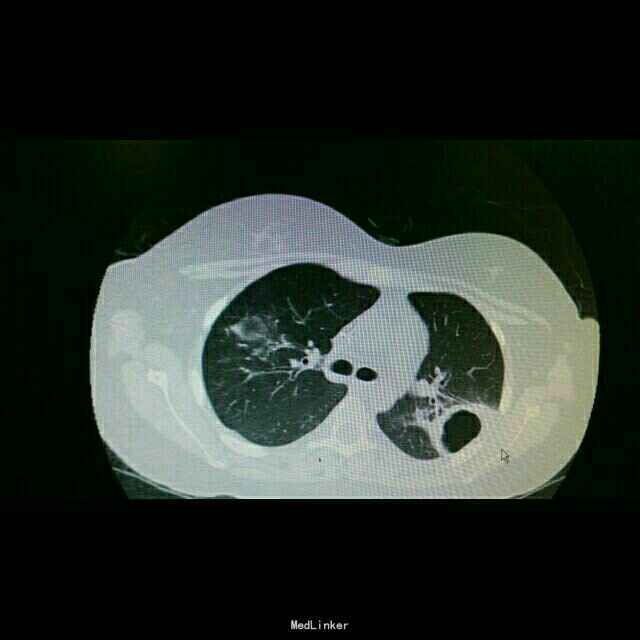

查体:双肺湿罗音,余无特殊。 辅查:9.10胸部CT双肺炎症。10.2原炎症部位出现空洞。10,21原炎症部位好转,空洞无明显变化。

诊断:肺曲霉病。 治疗:开始予以伏立康唑治疗,仍有发热,后予以两性霉素*B治疗。